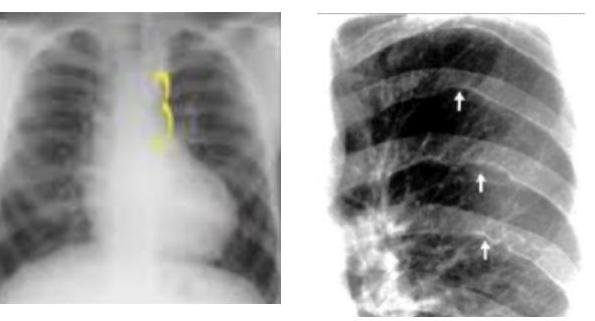

# COARTACIÓN DE LA AORTA ## DEFINICIÓN **Coartación de la Aorta** La coartación de la aorta es un estrechamiento que usualmente se localiza en la región del ligamento arterioso, adyacente al nacimiento de la subclavia izquierda y que puede estar asociada con hipoplasia difusa del arco aórtico o del istmo. En ausencia de circulación colateral abundante o extensa, se define como la presencia de **hipertensión en las extremidades superiores** asociada a un gradiente significativo extremidades superiores-inferiores de al menos **20 mm Hg**. Cuando existe abundante circulación colateral puede no existir gradiente en cuyo caso el diagnóstico se apoya con estudios de imagen. ## ETIOLOGÍA  Usualmente es de origen esporádico. - Puede asociarse a Sx de Turner, Sx de Williams-Beuren, Rubeola congénita, Neurofibromatosis, Arteritis de Takayasu o a Traumatismos. - Se puede presentar en otras anormalidades cardiovasculares como Aorta Bivalva y Aneurismas Intracraneales, alteraciones de la circulación **braquiocefálica**, circulación colateral, estenosis subaórtica y alteraciones de la válvula mitral. ## Existen dos teorías: - Reducción anterógrada del flujo sanguíneo intrauterino que ocasiona un pobre desarrollo del arco aórtico. - Constricción del tejido ductal que se extiende dentro de la aórtica torácica. ## EPIDEMIOLOGIA - Representa el 5-8% de todos los **defectos congénitos del corazón**. - La razón hombres: mujeres es de 1.5:1. - Forma parte de las **cardiopatías congénitas acianógenas** con flujo pulmonar normal y para ser más precisos se ubica dentro de las **obstrucciones izquierdas**. # CLÍNICA Dependerá de la severidad de la coartación. **HALLAZGOS CLÁSICOS**: - Hipertensión en las extremidades superiores. - Disminución o retardo de los pulsos femorales (retardo braquial-femoral). - Presión arterial no obtenible o disminuida en las extremidades inferiores. Otras: hipertensión, cefalea, mareo, tinnitus, epistaxis, disnea, angina abdominal,  claudicación, extremidades frías. **COARTACIÓN LEVE**: leve hipoplasia, ausencia de colaterales y sin gradiente o leve, tampoco hay hipertensión. **COARTACIÓN SEVERA**: marcada estrechez anatómica, presencia de ramificaciones colaterales, elevado gradiente e hipertensión significativa. ## ESTUDIOS DE IMAGEN GS: **ANGIOTOMOGRAFÍA DE TÓRAX** es el estudio más específico y sensible. ELECTROCARDIOGRAMA - Puede mostrar normalidad o hasta hipertrofia del ventrículo izquierdo con incremento del voltaje. - Cambios en el ST y la onda T en las derivaciones precordiales izquierda. ## RADIOGRAFÍA DE TÓRAX - Puede mostrar una muesca en el tercio posterior de la tercera a la octava costilla debido a la erosión ocasionada por el largo de las arterias colaterales (**Signo de Rösler**). Es más evidente a mayor edad del paciente. - La hendidura de la pared aórtica en el sitio de la coartación con la dilatación pre y post coartación producen el **SIGNO DEL 3** (causado por la indentación de la aorta en el sitio de la coartación, combinado con la dilatación pre y post coartación). ## Signo del 3 Se forma un 3 en el lugar preestenótico, el de la coartación y el postestenótico.  ## Signo de Rösler Escotaduras costales inferiores debido a tortuosidad de las arterias intercostales. ## ECOCARDIOGRAMA TRANSTORÁCICO - Es recomendado como estudio de imagen inicial para valorar la hemodinamia del paciente. - Puede ser demostrada en la ventana supraesternal apuntando hacia el arco aórtico. - Si se combina con doppler color y continuo se observa flujo turbulento en la porción proximal de aorta. - Útil para el procedimiento intervencionista ya que permite visualizar completa la aorta descendente, el balón e identifica complicaciones como la disección aórtica. ## RMN - Permiten visualizar la aorta en su mayor extensión, incluyendo el segmento coartado. - Brinda información anatómica para planear la intervención Qx o percutánea. (c) Copyright 2021-2022 Joyas ENARM - Todos los derechos reservados - # TRATAMIENTO FARMACOLÓGICO 1ra elección: **Betabloqueadores, IECA, ARA** + Manejo enfermedad primaria. Anticoagulantes: indicado en pacientes con **disfunción ventricular izquierda** y **alteraciones extensas de la movilidad parietal postinfarto** para evitar eventos tromboembólicos. Si persiste hipertensión posterior a intervención exitosa - **Metoprolol**. ## TRATAMIENTO INTERVENCIONISTA Se recomienda llevar a intervencionismo a todos los pacientes con coartación en las siguientes circunstancias: - Gradiente pico-pico de >20 mm Hg transcoartación. - Gradiente pico-pico < 20 mm Hg en presencia de imagen anatómica de coartación significativa con evidencia radiológica de circulación colateral significativa. ## TRATAMIENTO QUIRÚRGICO 1ra elección: **Intervención percutánea Transcatéter**. Indicada en gradiente pico al menos de 20 mmHg. 2da elección: **Cirugía**. ## COMPLICACIONES - Formación de **aneurismas** postintervención en el sitio afectado ( 0-55 % ). - Factores predisponentes:daño a pared vascular por balón de angioplastía, necrosis quística de la media. - Sangrado postquirúrgico temprano. - Derrame pleural. - Contusión pulmonar. - Parálisis del nervio laríngeo recurrente. - Parálisis del nervio frénico. - Formación de pseudoaneurisma en sitio de reparación. ## Recoartación - Se presenta como consecuencia de la proliferación neointimal excesiva en el sitio quirúrgico de la anastomosis o en respuesta al trauma vascular durante la intervención percutánea exacerbado por retracción elástica.